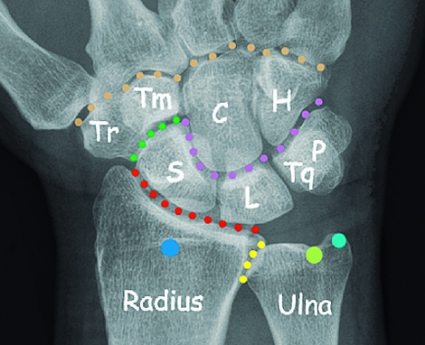

Handleden består av distala radius och ulna, distala radioulnarleden, radiokarpalleden, carpus med proximala karpalbensraden (scaphoideum, lunatum, triquetrum och sesambenet pisiforme), den rörliga midkarpalleden, den distala karpalbensraden (trapezium, trapezoideum, capitatum, hamatum) och traditionellt även karpometakarpallederna (CMC).

Carpus tillhör kroppens mest komplicerade ledsystem, och denna artikulation kan ställa in handen i exakt finmotoriskt läge samtidigt som en tiofaldig kraftöverföring kan ske från fingertopparna till mellanhanden. 80 procent av denna kraft överförs vidare mellan carpus och radius. I normalfallet överförs resterande 20 procent mellan carpus och ulna.

Radius roterar runt ulna, som ligger still. Ulna är viktig för stabilitet och rörelse men är inte utformad för att ta upp axiala krafter. Distala radioulnarleden är däremot direkt kraftbärande vid lyft med flekterad armbåge och neutralt roterad underarm. Inga senor fäster i proximala karpalbensraden, och här bidrar inte musklerna med någon dynamisk stabilitet. Stabiliteten beror i stället helt på den speciella benanatomin och de starka ligamenten mellan scaphoideum, lunatum och triquetrum.

Mellan benen i distala karpalbensraden, där handledens extensor- och flexorsenor fäster, finns ingen inneboende spänning eller någon nämnvärd rörlighet. Dessa ben rör sig mer som en gemensam enhet. Flexion/extension i handleden tas till 60 procent ut i radiokarpalleden. Resterande 40 procent av rörelseuttaget äger rum i midkarpalleden, dvs mellan proximala och distala karpalbensraden [7].

Scaphoideum är det enda ben som överbryggar de två karpalbensraderna. Scaphoideum fungerar därigenom som en länk mellan dem, vilket ger en stabiliserande effekt. Utan intakt scaphoideum eller skafolunärt ligament skulle carpus vara instabil, särskilt då den utsätts för kompressionskrafter. En s k karpal kollaps skulle då lätt kunna uppkomma. Trots sin stabiliserande effekt är scaphoideum mycket rörlig: 45° i två plan. Vid radialdeviation av handleden sker exempelvis en kraftig volarflexion av scaphoideum.

I carpus finns ett tjugotal väldefinierade ligament som bidrar till styrka och stabilitet. Dessa är uppdelade i extrinsic- och intrinsic-ligament. Extrinsic-ligamenten har sitt ursprung på radius eller ulna och fäster i carpus. Intrinsic-ligamenten har både ursprung och fäste inom carpus. Dessa är oftast tvärgående och djupt liggande ligament som förbinder två angränsande ben inom samma karpalbensrad.

Viktiga ligament i den proximala karpalbensraden är skafolunära ligamentet (mellan scaphoideum och lunatum) och lunotrikvetrala ligamentet, som förbinder lunatum med triquetrum. Den dorsala portionen av skafolunära ligamentet är starkast, medan den volara portionen av lunotrikvetrala ligamentet är starkast.